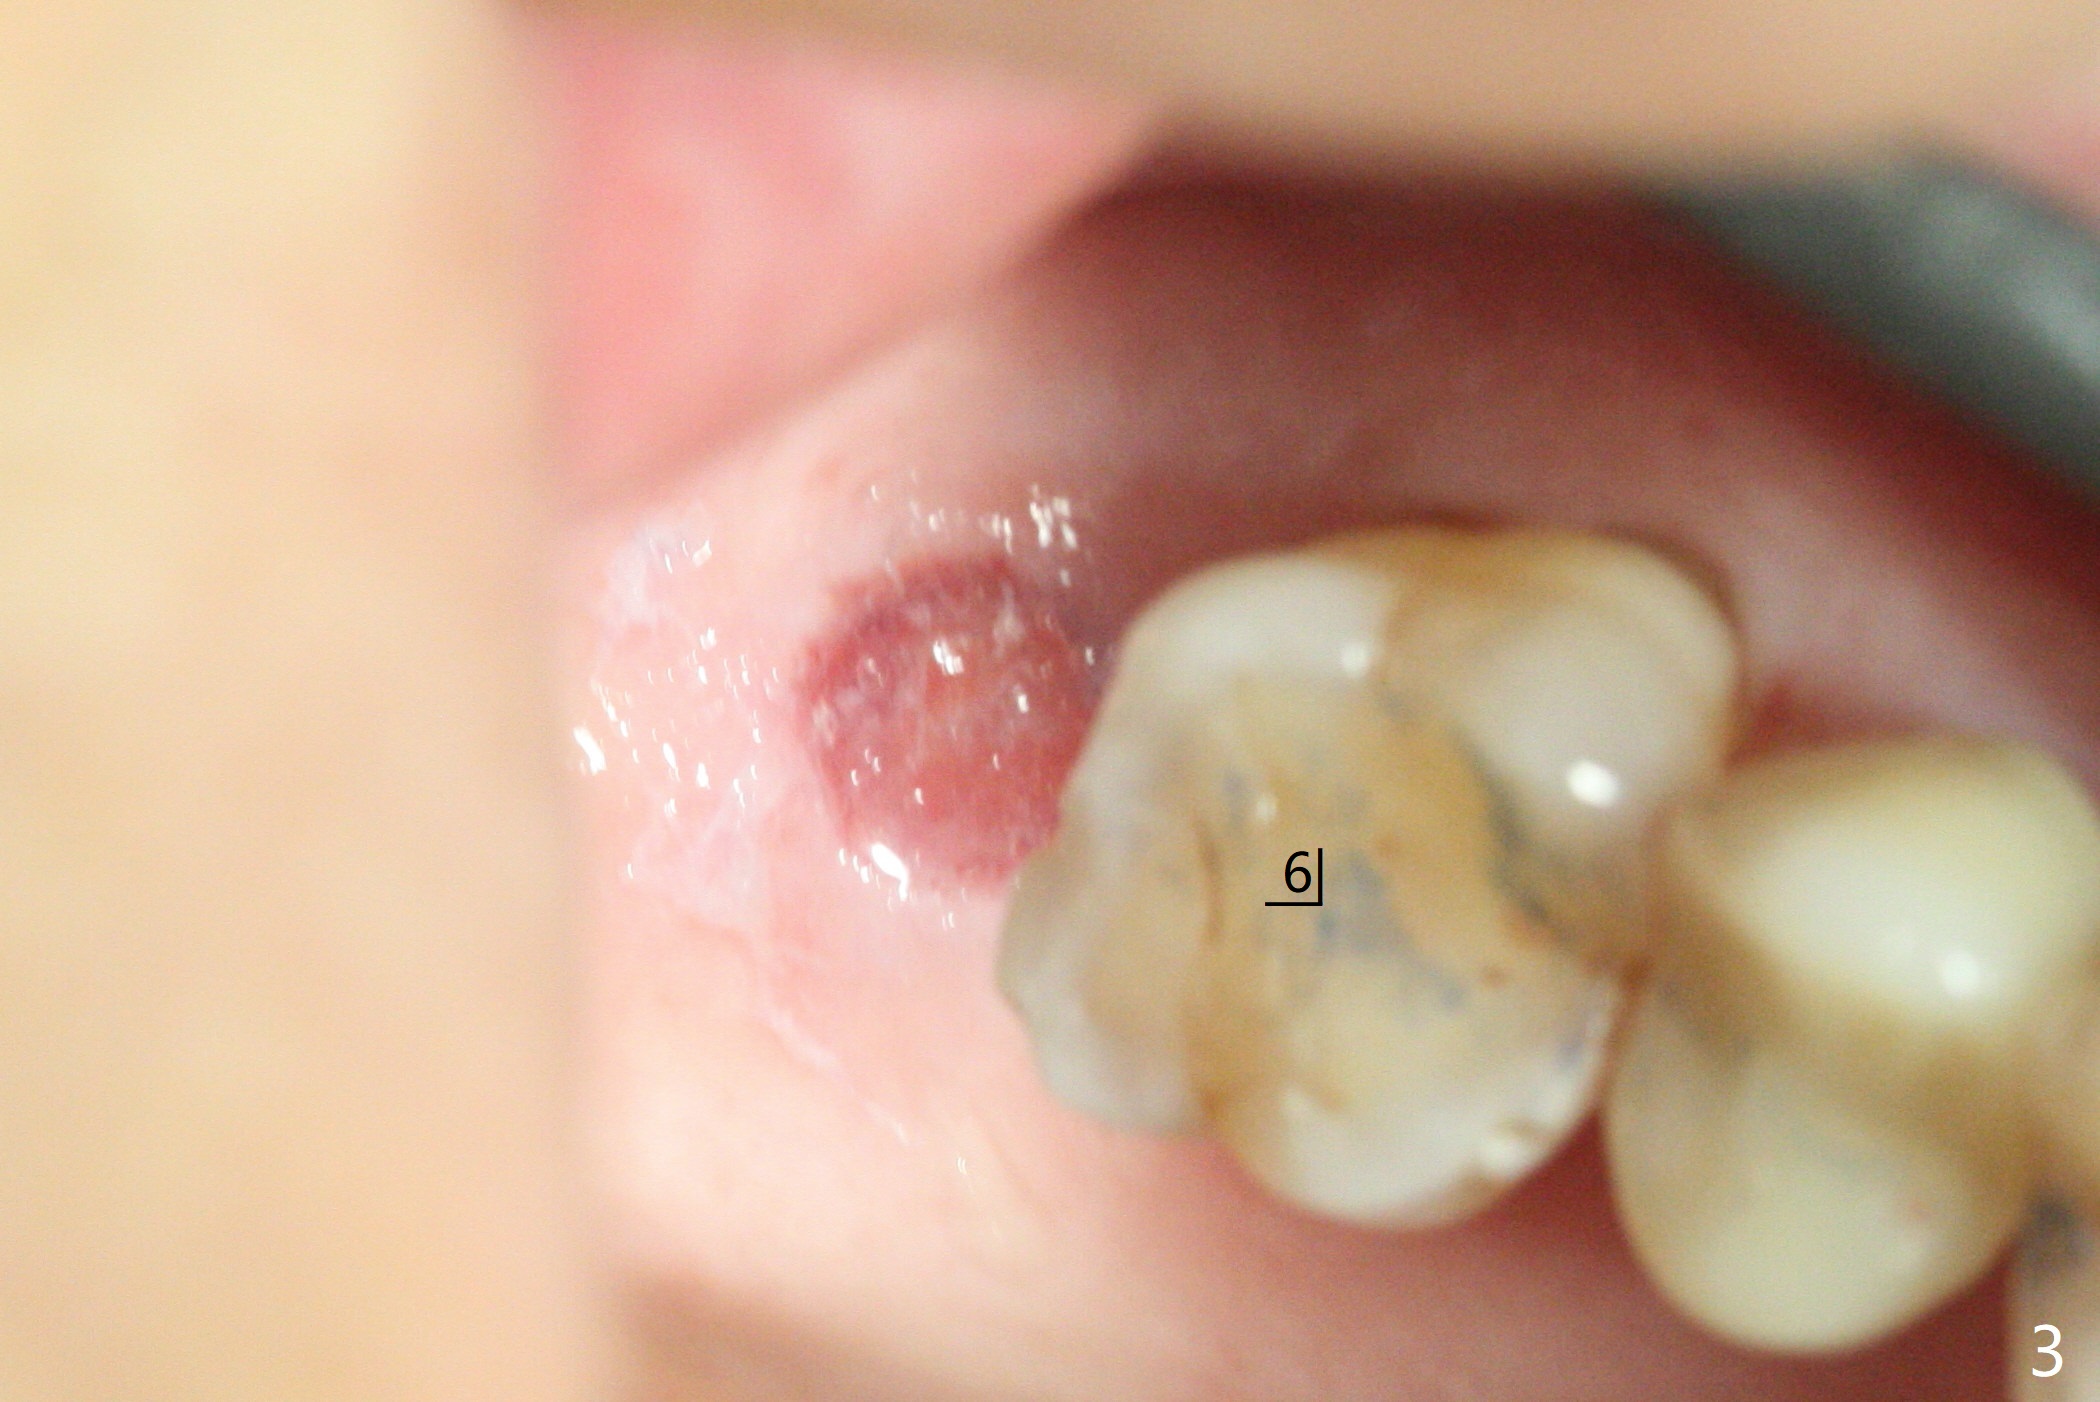

66岁男右上,左上7导板延期种植(足够角化龈,使用环形切刀),都提升,但是前者未植骨(图一,二(骨高度多,进入上颌窦少)),后者植骨(图六(*),七),由于扭力低(小于15Ncm),放置愈合螺帽和剪成圆形六个月胶原膜,使用牙周胶水(图三,八),之后不再放置牙周敷料。当钻头接近左侧上颌窦底板时,放置骨粉(图四-六:*),使用报废植体(图四,五)和正式植体(图六)将骨粉推入上颌窦。术后病人抱怨食物撞击伤口疼痛,即刻修复减少术后疼痛。术后5个月没有骨质吸收,基台完全就位(图十一,二)。